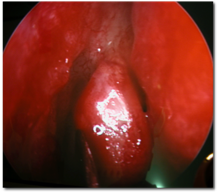

DACRIOCISTORRINOSTOMÍA ENDONASAL (DCR-ENDO)

En este caso, la cirugía se hace a través de la fosa nasal. Desde allí se perfora la mucosa nasal y el hueso de la nariz hasta el saco lagrimal.

La ventaja es la ausencia de cicatriz en la piel.

![]() |

| DCR Endonasal | |

Desventajas: en fosas nasales muy estrechas, o en traumatismos, es más difícil su realización.

Ante una sospecha de tumoraciones en el saco lagrimal no estaría indicada.

Se realiza con anestesia local y sedación.

Al final de la cirugía se colocan los tubitos de silicona.